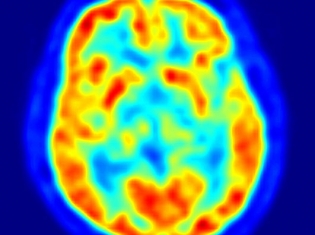

The study's volunteers are participating in the National Institute of Aging’s Baltimore Longitudinal Study of Aging (BLSA), which is the lengthiest scientific study of human aging to date. The researchers analyzed blood samples of 57 older, symptom-free volunteers to determine whether specific proteins were associated with amyloid burden in the brain. Then, they measured brain amyloid using PET (positron emission tomography) scans with Pittsburgh Compound B, a tracer that binds to amyloid plaques.